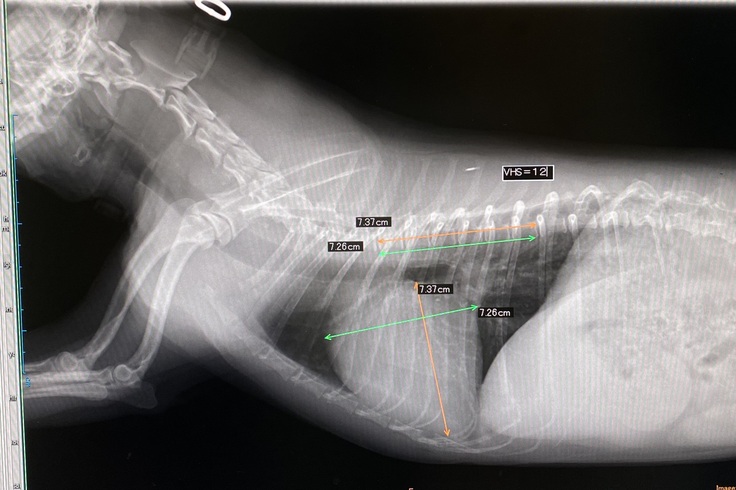

上記画像はシェリーのレントゲンでございます。VHSという部分ですが、主治医のお話ですと通常の子の心臓であれば数値は10.5ほどのようですが、シェリーは心臓が肥大しているため12という数値になっております。これはステージCという内服薬治療、そして外科手術が必要なレベルだと言われました。